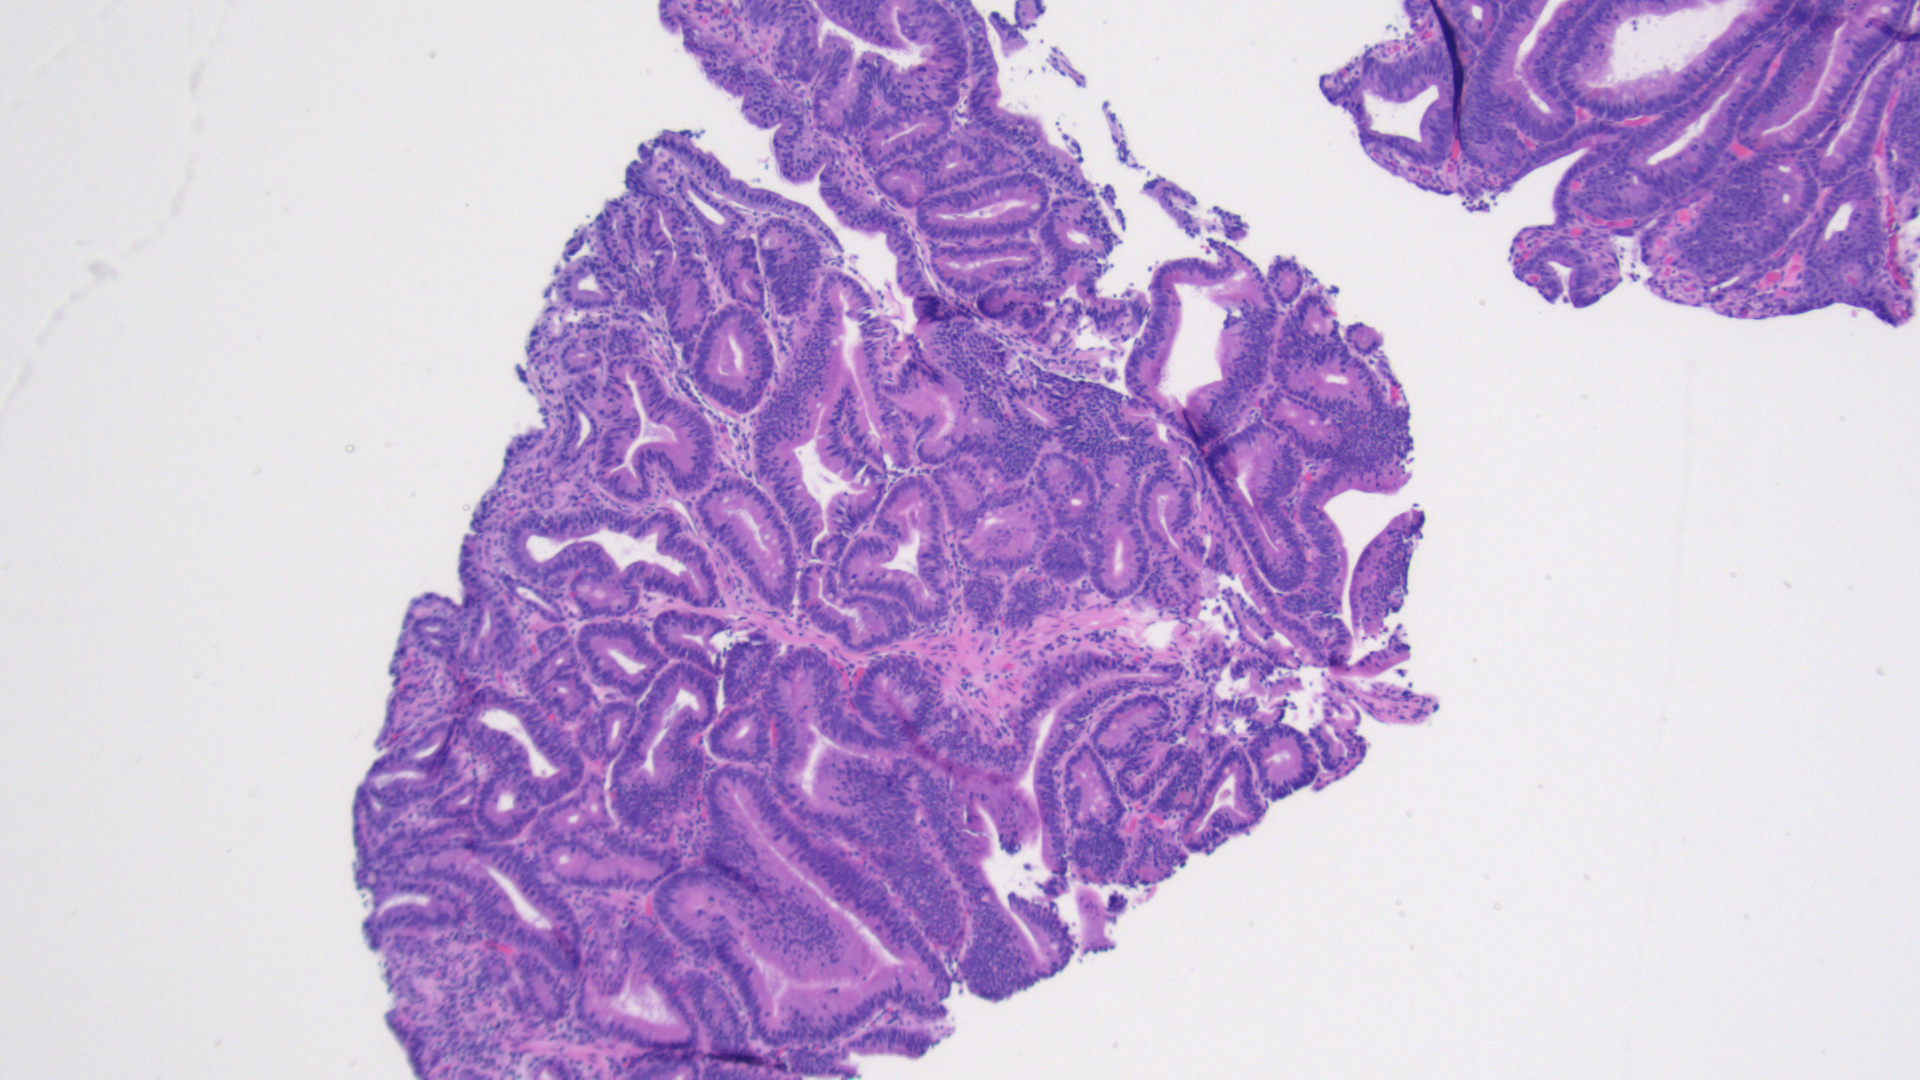

Tissue track samples resulted in the diagnosis of ampullary adenoma without evidence of high-grade dysplasia (Figures 4,5), and cytology from the brush biopsy showing atypical glandular cells. CA 19-9 levels decreased from 152 to 25 units/ml one month post-procedure. Due to a diagnosis of ampullary adenoma, the patient and her family were counseled on ampullectomy to prevent ampullary cancer versus watchful waiting. They elected to pursue ampullectomy. The procedure was performed under general anesthesia. A side viewing duodenoscope was advanced to the second part of the duodenum. The previously placed biliary stent was retrieved using a snare.  The scope was then repositioned to visualize a large 3.5 cm ampullary adenoma (Fig 1). Cholangioscopy (spyglass Boston Scientific) also revealed possible skip lesions versus changes from the prior stent in the bile duct.  Submucosal injection was then performed and the lesion lifted from the wall showing that it was not fixed to the side of the duodenum.  A 27 mm Captivator snare was used to perform ampullectomy which was retrieved using a Roth net.  A residual lesion on the margin was removed using a 15 Captivator, also retrieved using a Roth net.  After ampullectomy, cannulation of the pancreatic duct was achieved using Jagwire Revolution (Boston Scientific), after which a 5 cm French single pigtail pancreatic stent was placed.  The bile duct was also cannulated, after which double-pigtail 7 cm 10 French plastic biliary stent was placed with good biliary drainage (Figures 2,3).  Margins were ablated using Argon plasma coagulation to prevent adenoma recurrence. Histopathology showed intestinal type ampullary adenoma with low grade dysplasia and no invasive adenocarcinoma (Figures 6,7). One month later, ERCP was conducted during which both the double and single pigtail stents were removed, and further interrogation of the bile duct with cholangioscopy revealed no skip lesions suggesting that the observed small changes were due to the previous metal stenting. A 60mm x 10mm self-expanding metal biliary wall stent (Boston Scientific) was placed with good biliary drainage. The patient tolerated both procedures well without any adverse event.

Figure 4 - Initial ampullary biopsy, 40x magnification

Figure 5 - Initial ampullary biopsy, 100x magnification